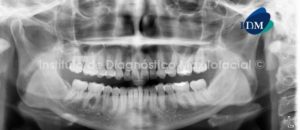

Paciente femenino de 31 años de edad es referido al Instituto de Diagnóstico Maxilofacial (IDM) para evaluación general y por presentar movilidad de la pieza